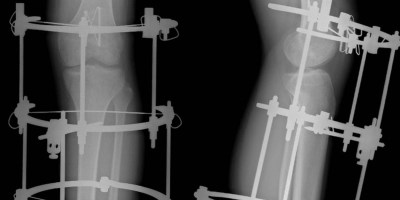

Allungare gli arti? Possibile